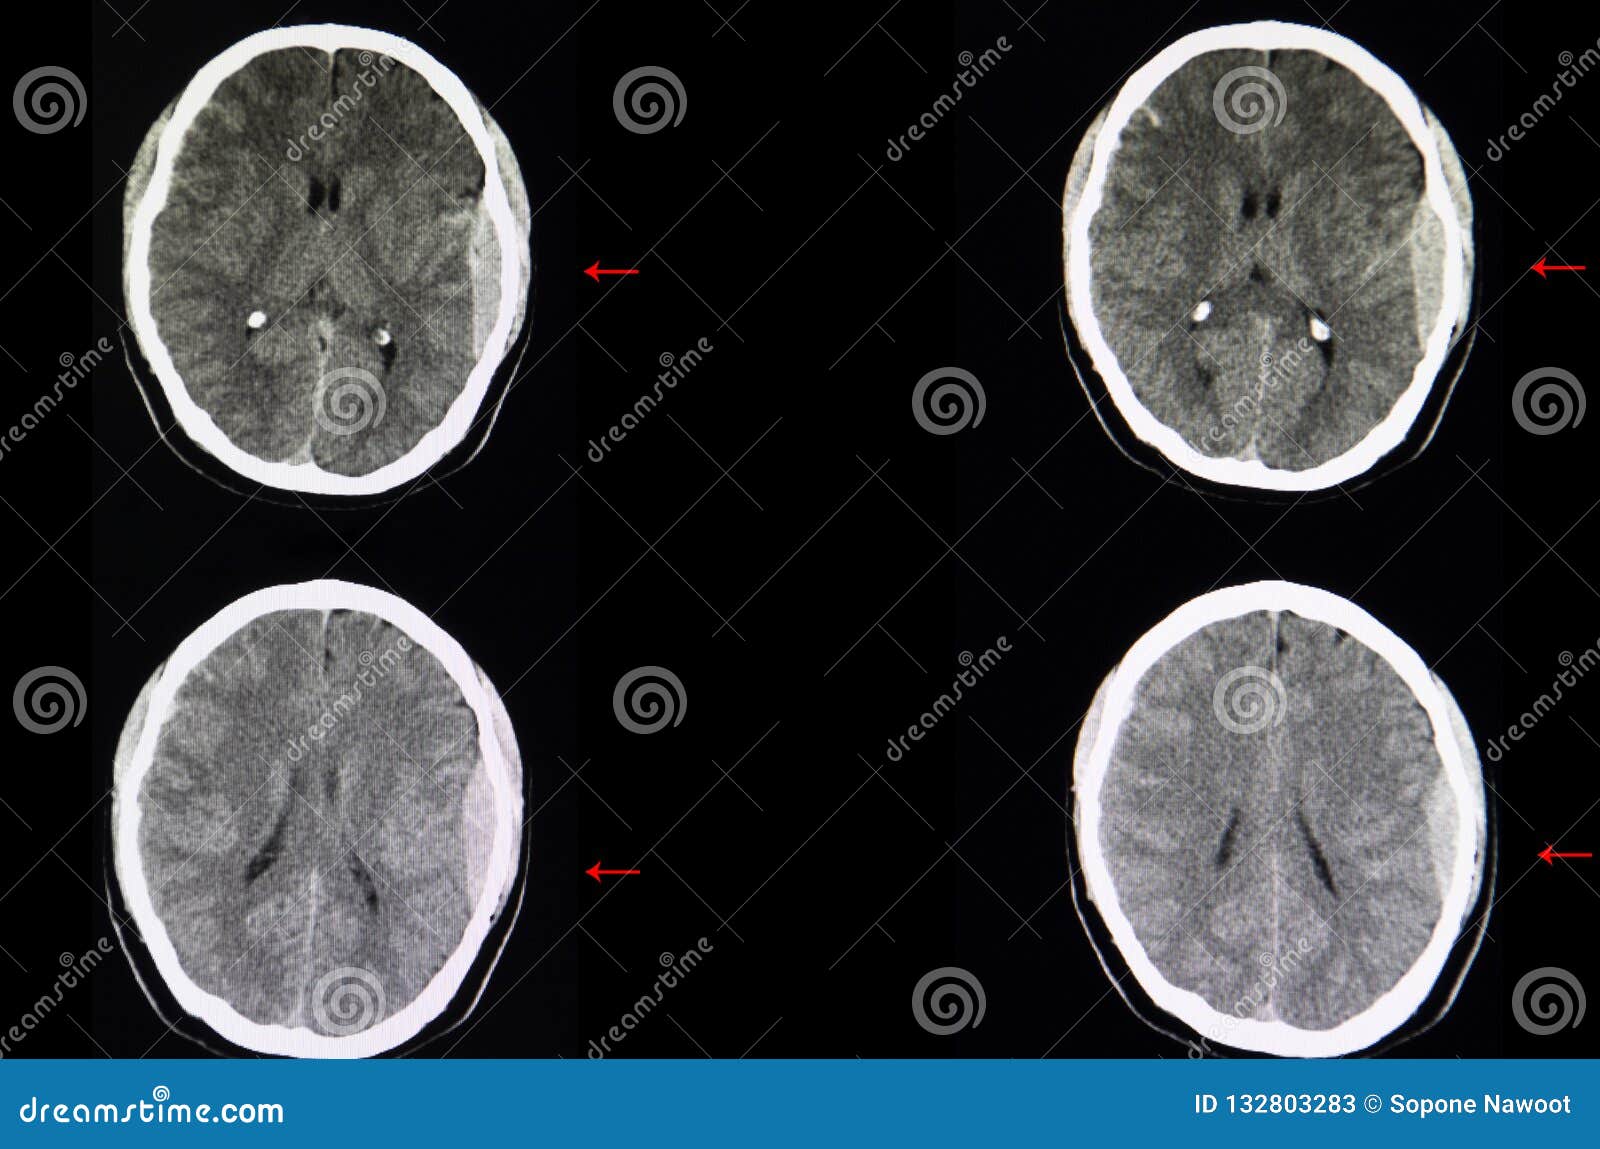

Devo Ripetere La Tac Empills Pillole Di Medicina D Urgenza